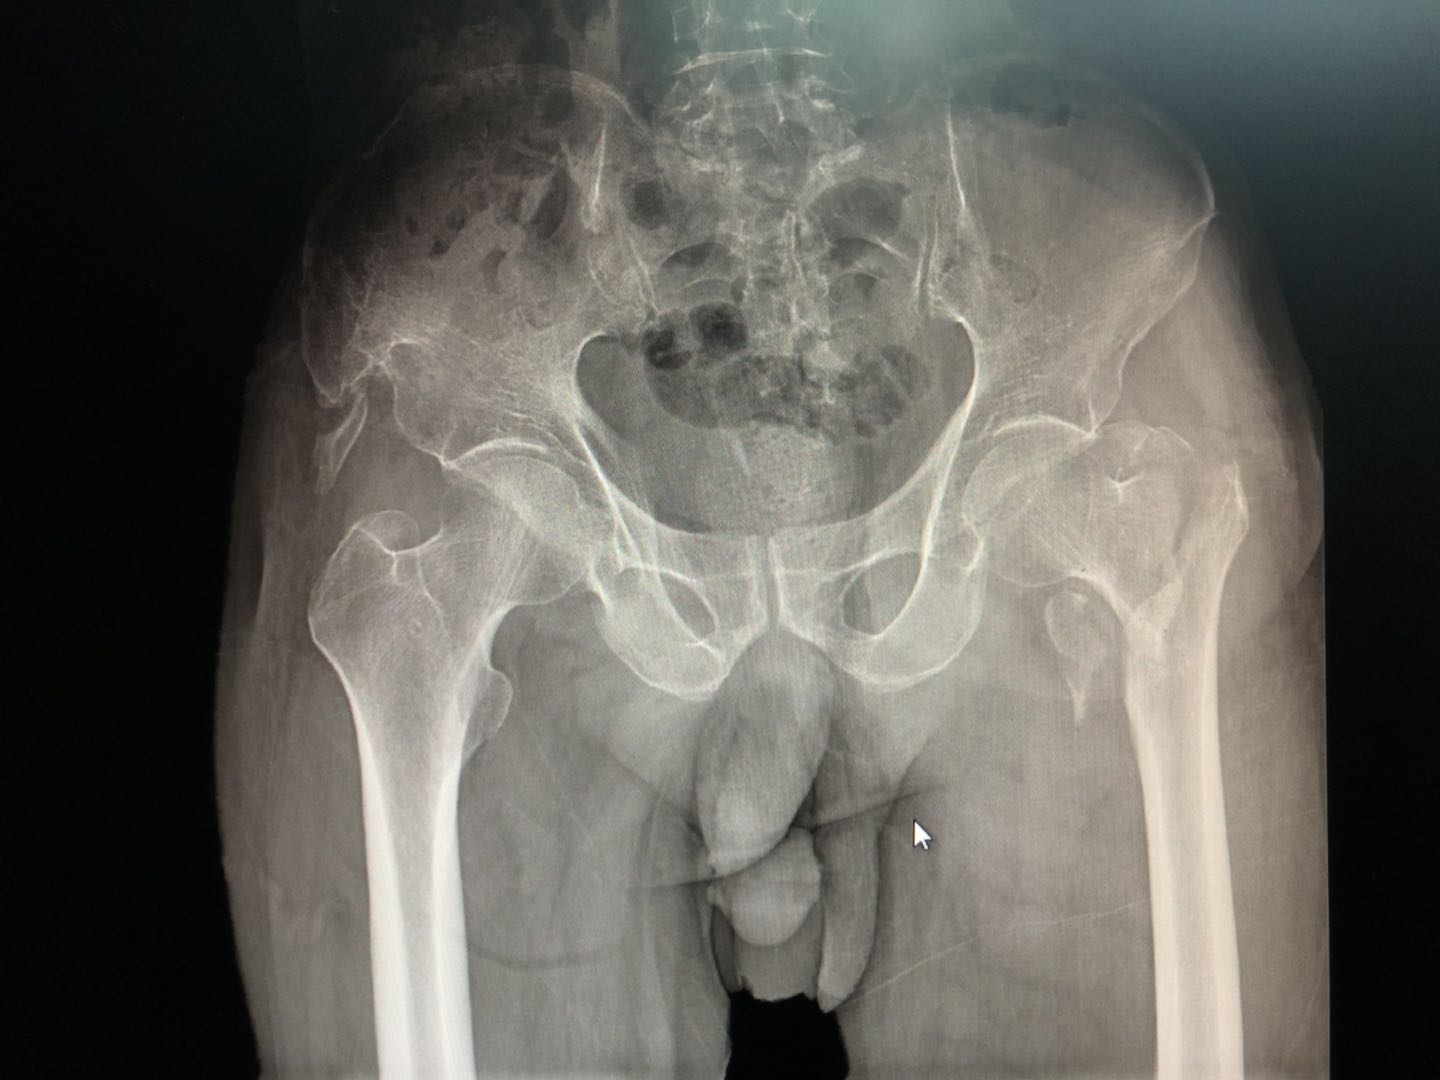

当地医院给冯大爷拍了一个骨盆正位片子结果如下:

左侧股骨粗隆间骨折

检查结果提示左侧股骨(大腿骨)的粗隆间骨折!这个跟股骨颈骨折严格意义上可以算是两个东西,但在老百姓眼中没有区别,就是骨头断了。